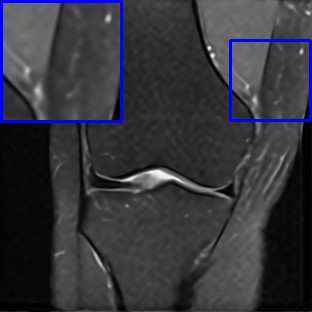

Limited by imaging systems, the reconstruction of Magnetic Resonance Imaging (MRI) images from partial measurement is essential to medical imaging research. Benefiting from the diverse and complementary information of multi-contrast MR images in different imaging modalities, multi-contrast Super-Resolution (SR) reconstruction is promising to yield SR images with higher quality. In the medical scenario, to fully visualize the lesion, radiologists are accustomed to zooming the MR images at arbitrary scales rather than using a fixed scale, as used by most MRI SR methods. In addition, existing multi-contrast MRI SR methods often require a fixed resolution for the reference image, which makes acquiring reference images difficult and imposes limitations on arbitrary scale SR tasks. To address these issues, we proposed an implicit neural representations based dual-arbitrary multi-contrast MRI super-resolution method, called Dual-ArbNet. First, we decouple the resolution of the target and reference images by a feature encoder, enabling the network to input target and reference images at arbitrary scales. Then, an implicit fusion decoder fuses the multi-contrast features and uses an Implicit Decoding Function~(IDF) to obtain the final MRI SR results. Furthermore, we introduce a curriculum learning strategy to train our network, which improves the generalization and performance of our Dual-ArbNet. Extensive experiments in two public MRI datasets demonstrate that our method outperforms state-of-the-art approaches under different scale factors and has great potential in clinical practice.